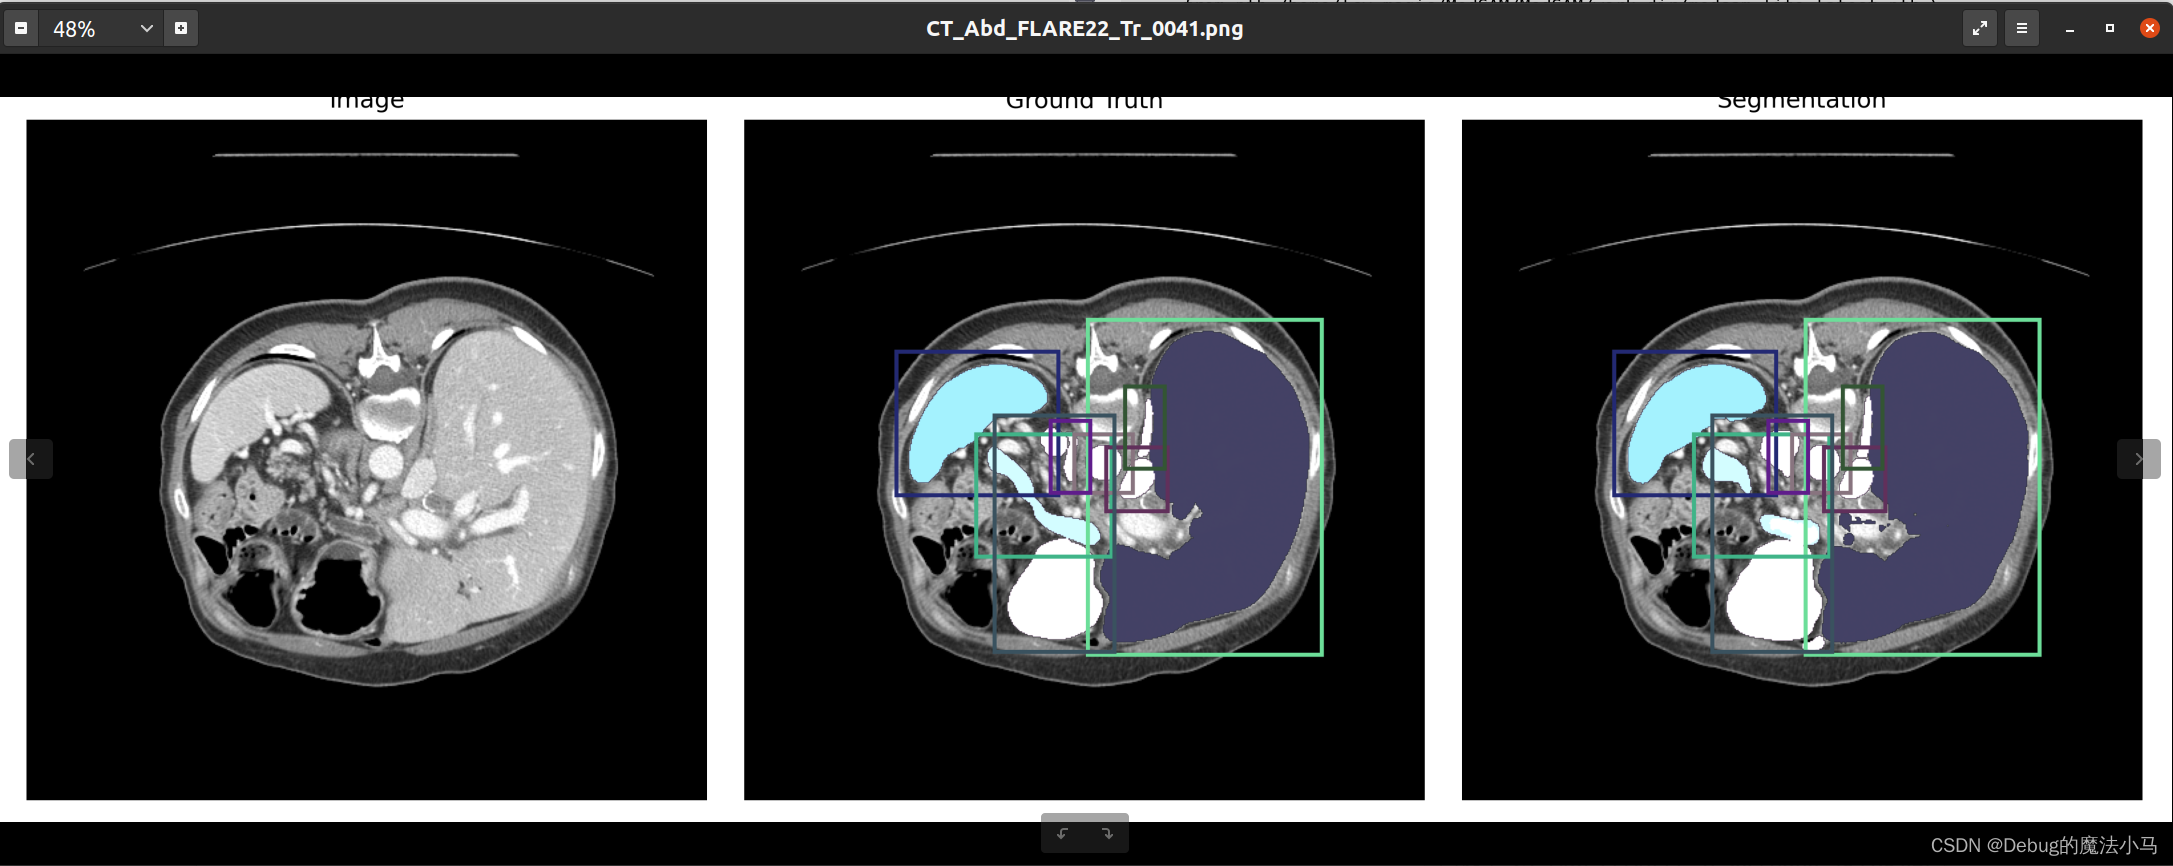

我把save_overlay参数设为True,运行后:

似乎没啥问题。暂时先这样了。

然后运行inference_3D.sh,成功: